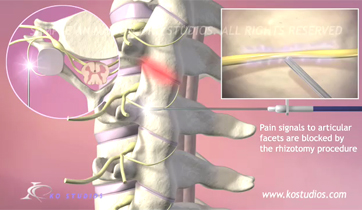

Cervical Facet Syndrome and Rhizotomy

Courtroom Animation for Law firm

This animation was created to be used as demonstrative evidence in a personal injury case. Visual aids such as this can help the jury understand complex medical injuries and procedures. We can customize each animation to be case specific.